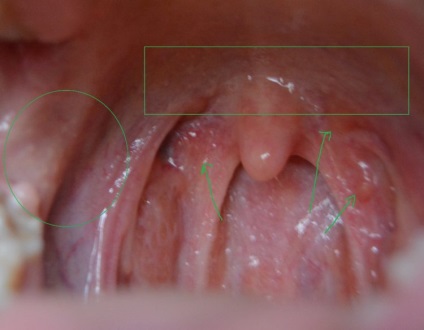

Blistere pe cerul gurii în gură: fotografie